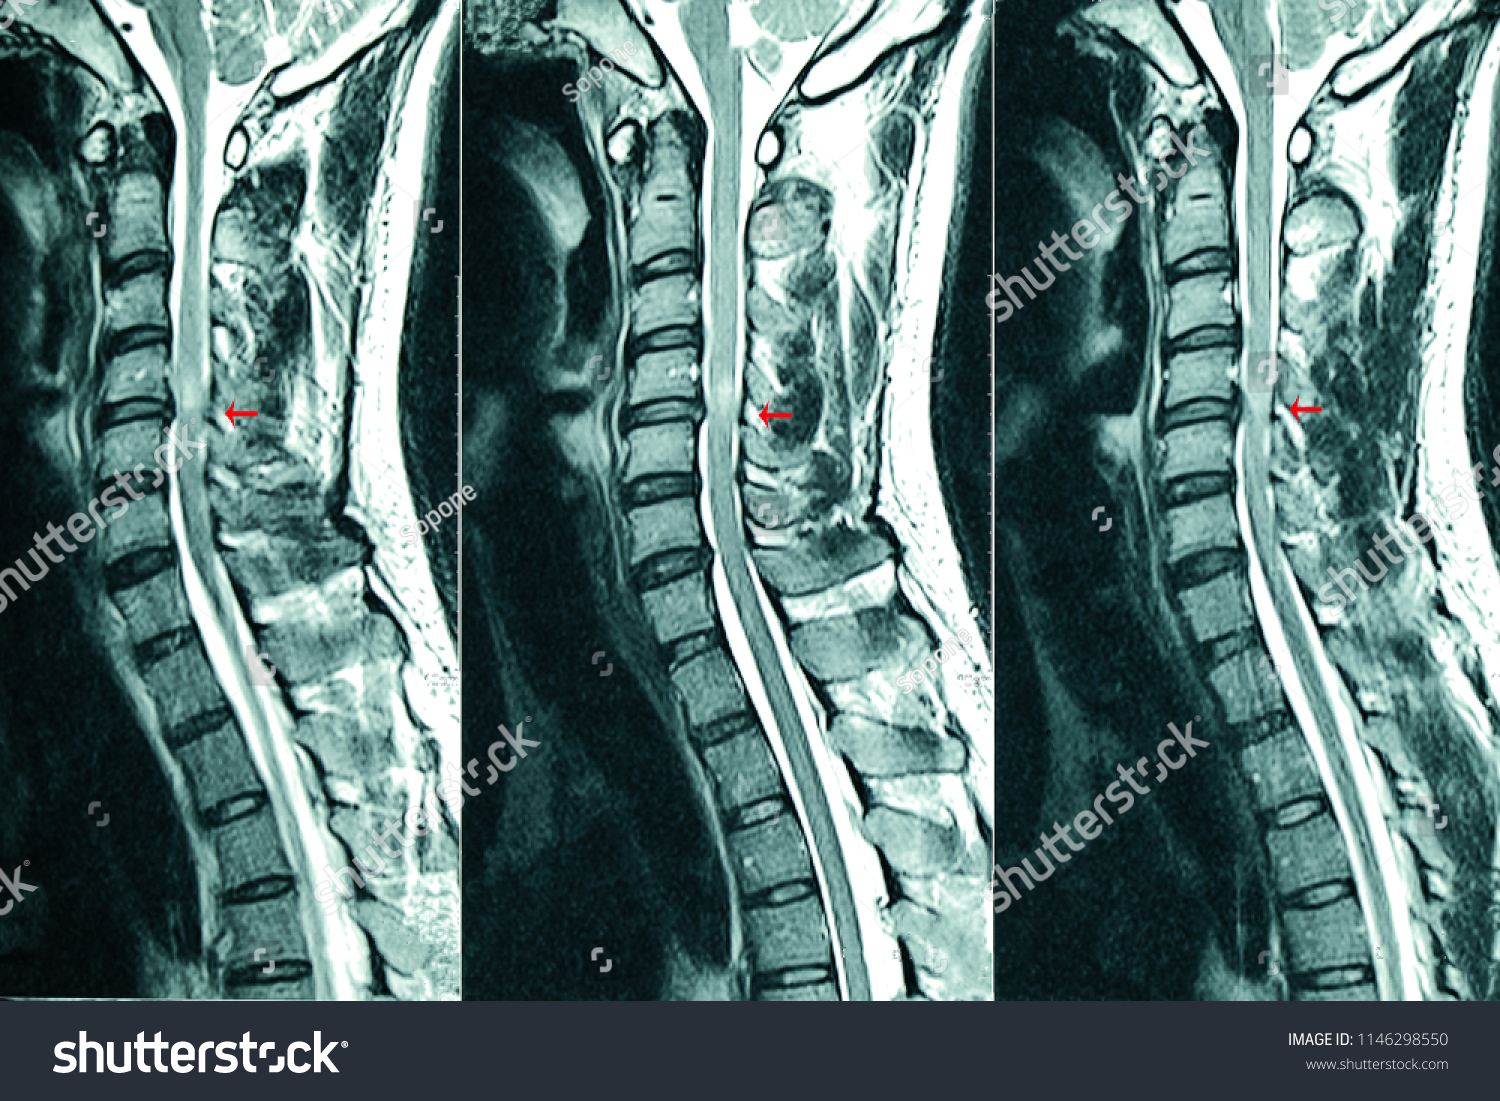

From www.shutterstock.com

C Spines Mri Scan Patient Chronic Stock Photo 1146298550 Shutterstock C Spine Mri Reddit Should i push for t spine as well? My neuro ordered a spine mri, but only cervical spine. This case illustrates the normal anatomy features found in the cervical spine mri. The cervical spine is the portion of your spine that runs through your neck. A cervical spine mri scan is used to help diagnose:. This section of the website. C Spine Mri Reddit.